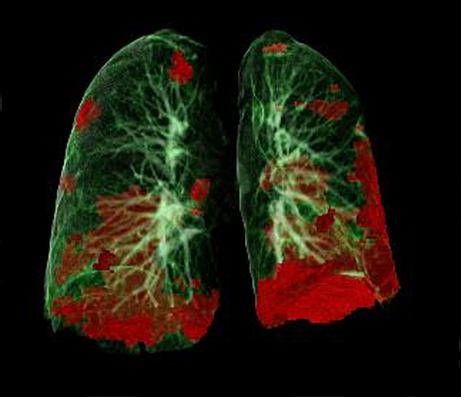

- Interdisziplinäre Zusammenarbeit aus Pneumologie, Infektiologie und Radiologie ermöglicht systematische Bewertung der Folgeschäden an der Lunge

In Zusammenarbeit mit dem Team um den Radiologen Gerlig Widmann, zeigten sich in den CT-Untersuchungen sechs Wochen nach Krankhausentlassung bei 88 Prozent der Patient:innen anhaltende leicht- bis mittelgradige strukturelle Veränderungen der Lunge, Diese bildeten sich allerdings im Zeitverlauf bei den meisten Patient:innen deutlich zurück. Es gibt derzeit keine Hinweise auf fortschreitende Lungenschäden, wie etwa zunehmende Vernarbungen. Ob die Veränderungen in der Lunge und die damit verbundene Einschränkung der Lungenfunktion vollständig abklingen werden, ist aktuell noch nicht zur Gänze zu beantworten und wird in weiteren Untersuchungen analysiert werden.